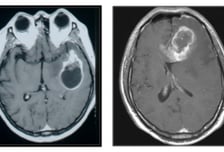

메스껍고 토악질, 가벼이 넘겼는데…뇌종양이라고요?

7월22일은 '세계 뇌의 날'이다. 뇌종양은 흔히 불치병으로 여겨지며, 교모세포종과 같은 악성 뇌종양은 5년 생존율이 10% 미만으로 매우 낮다. 그러나 매년 발생하는 뇌종양 환자 10명 중 7~8명은 성장이 느린 '양성'으로, 비교적 예후가 좋은 종양이 대부분이다. 서울대병원 신경외과 박철기 교수의 도움말로 뇌종양의 유형별 특징과 치료법, 조기 발견을 위한 주의 신호를 알아본다. ━양성일 땐 5년 생존율 90% 이상━뇌종양은 뇌뿐만 아니라 뇌막·뇌신경·두개골·두피 등에 발생한 종양이다. 발생 경로에 따라 △원발성(뇌와 주변부에서 발생) △전이성(다른 장기로부터 전이됨)으로 나뉜다. 그중 '원발성 뇌종양'은 다른 장기로 전이되지 않고 뇌·척수 등 중추신경계 안에서만 재발한다. 뇌종양의 가장 흔한 증상은 '두통'이다. 종양이 커지면서 두개골 내 뇌압을 올려 반복적·점진적·지속적인 통증을 유발한다. 일상적인 두통과 구별하려면 통증 추이에 주목해야 한다. 진통제를 먹어도 효과가 없고, 통